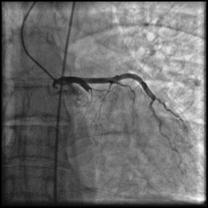

Рисунок 7. Ангиографические признаки окклюзии коронарных артерий при ОКС.